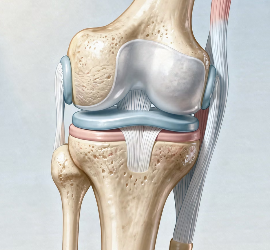

2. 인대나 힘줄 움직임

무릎을 움직일 때 인대나 힘줄이 뼈 위를 지나가면서 소리가 날 수 있습니다.

특히 운동을 하거나 자세를 바꿀 때 이런 소리가 발생하는 경우가 있습니다.

무릎 관절에는 충격을 흡수하는 연골이 있습니다.

연골이 약해지거나 마찰이 증가하면 움직일 때 소리가 발생할 수 있습니다.